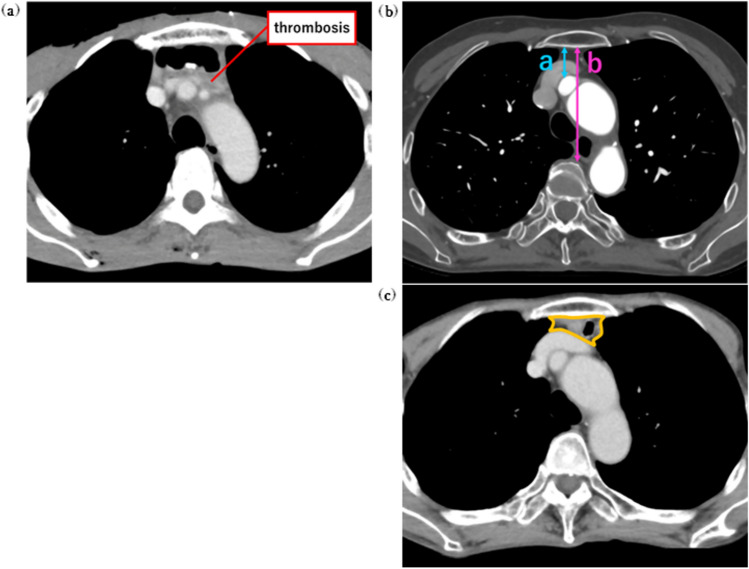

Methods: Seventy-five cases of thoracic esophageal cancer who underwent one-stage curative resection and reconstructive surgery from May 2019 to June 2022 were included. The stomach or ileocolon was selected as the reconstructive graft. All cases requiring chemotherapy were treated with a peripheral central venous catheter (PICC). To evaluate the width of the retrosternal space, the retrosternal ratio and the cross-sectional area of the graft intestine were measured at the level of the left brachiocephalic vein.

Results: UEDVT was observed in 11 patients (14.7%) and occurred only with gastric tube reconstruction (p = 0.02). The width of the retrosternal space was significantly different between the UEDVT and non-UEDVT groups (p = 0.002). The cross-sectional area of reconstructive organ was larger in the stomach than in the ileocolon (p < 0.01). Patients with a history of PICC insertion from the left side had a higher incidence of UEDVT (p = 0.025).

Conclusions: In esophagectomy, gastric tube reconstruction, a retrosternal ratio less than 0.16, and history of PICC insertion from the left side are risk factors for UEDVT.